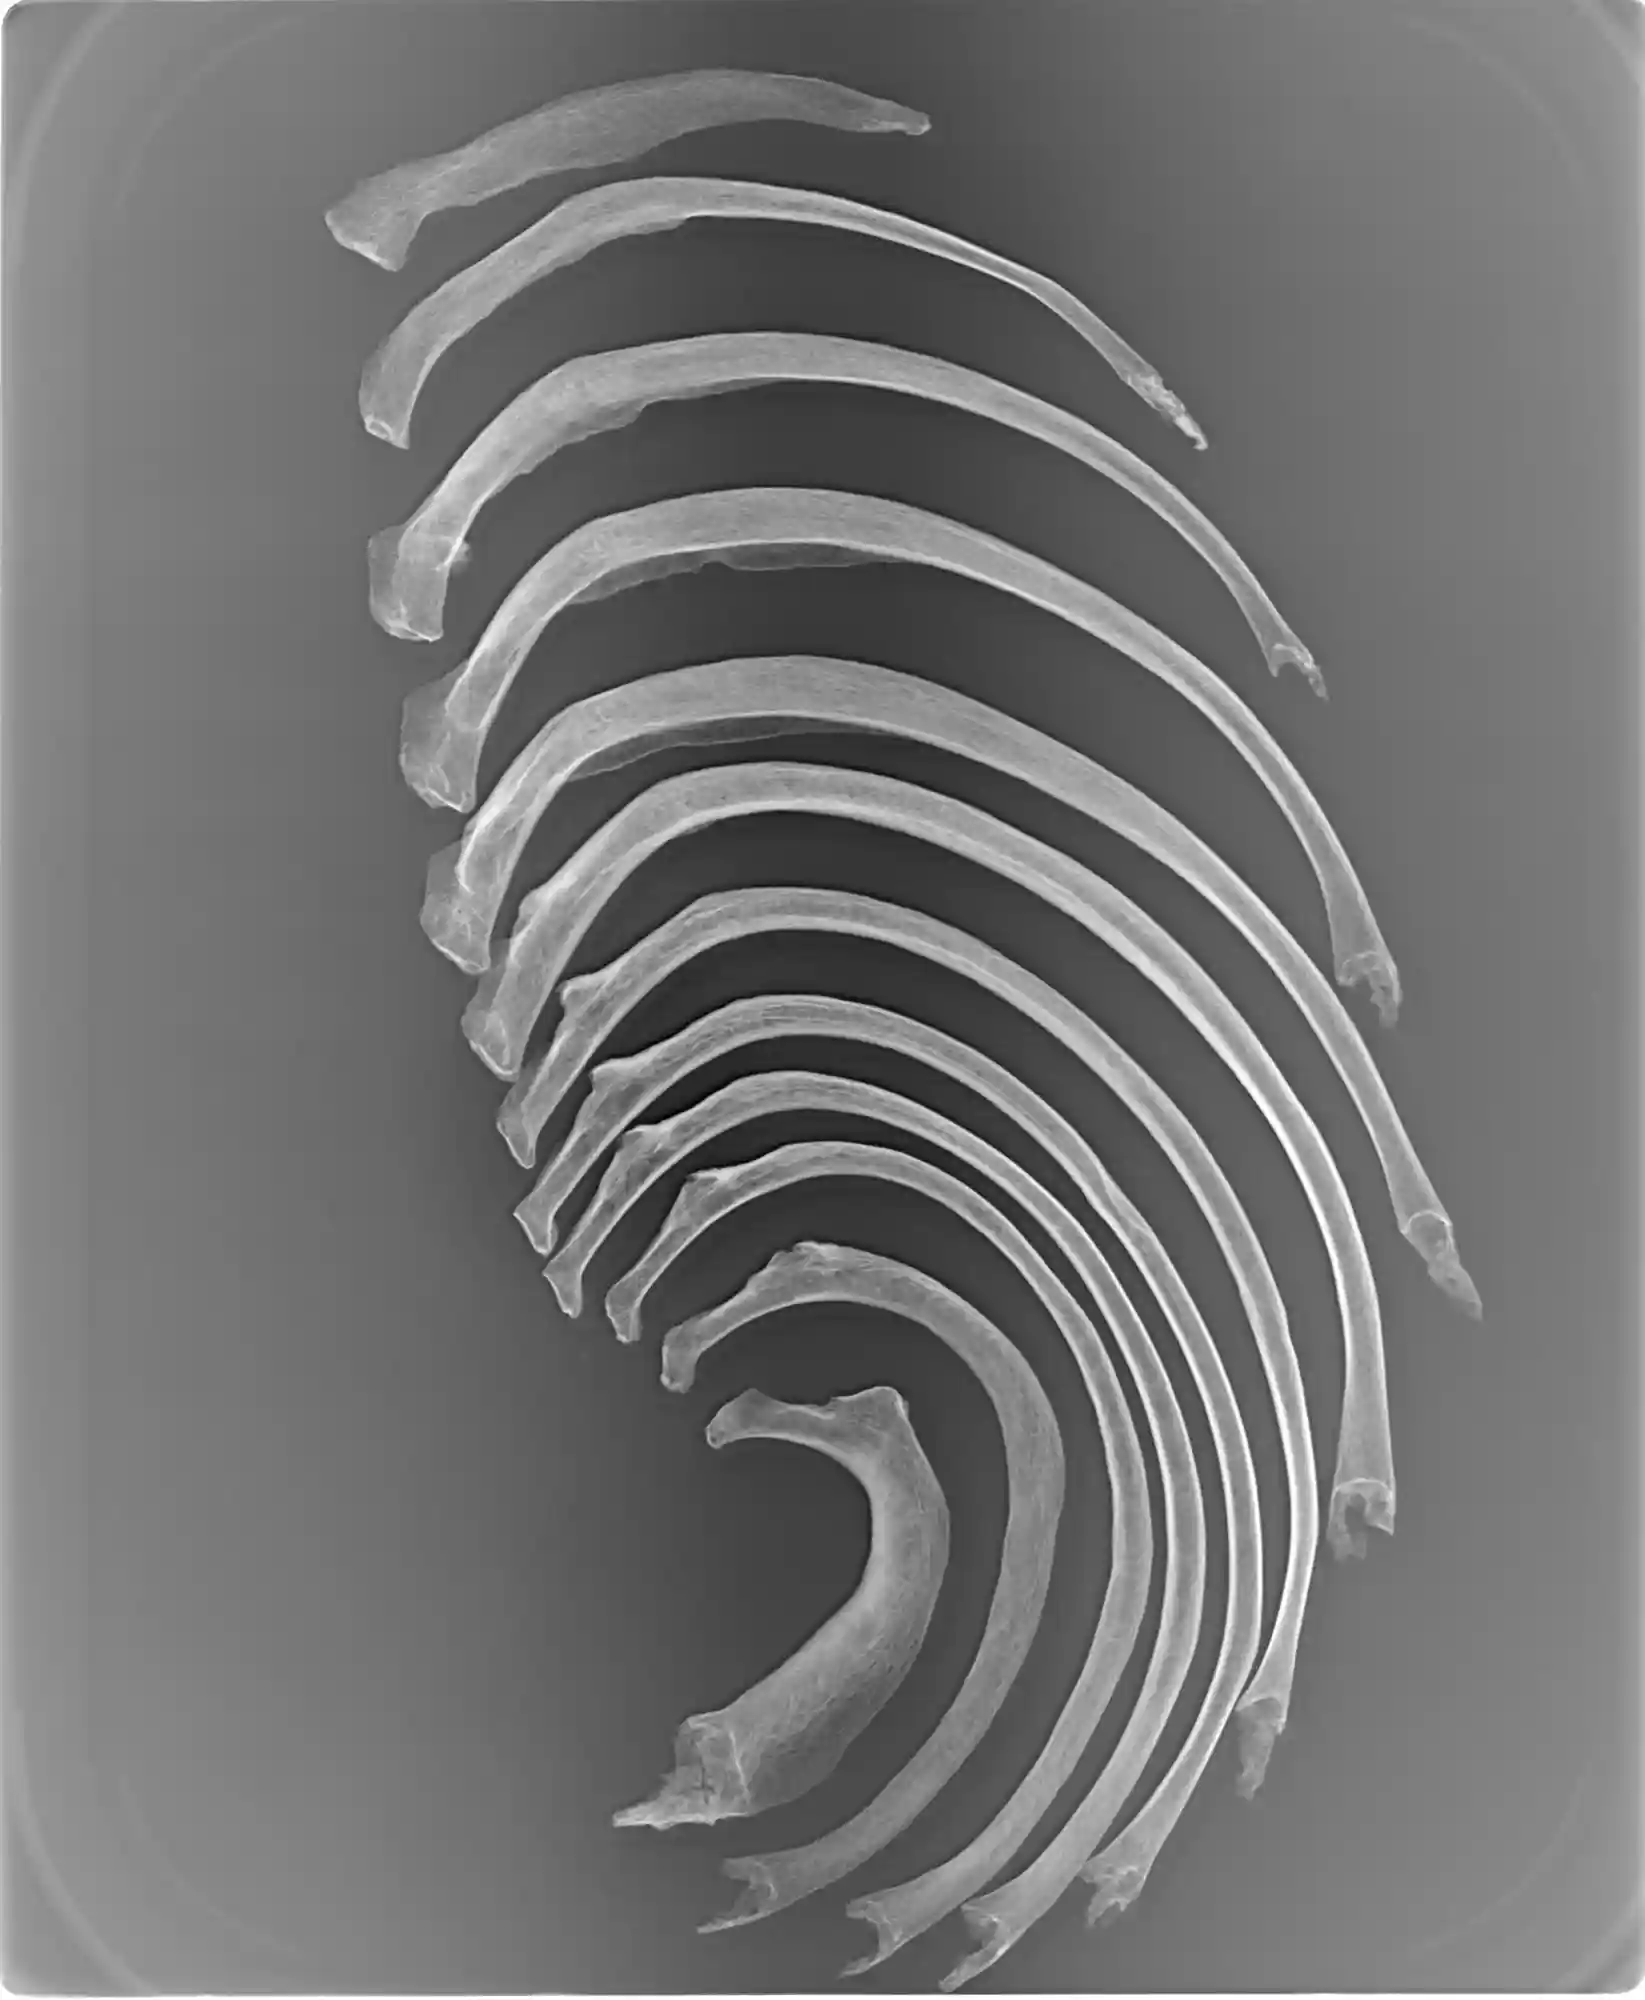

Forensic imaging techniques allow researchers to observe human skeleton variations, analyze hard tissue such as bone, and teeth, as well as for investigating human remains to solve criminal cases.

Forensic anthropology is the study and examination of human remains that involves applying skeletal analysis and techniques in archaeology to help law enforcement agencies with the recovery of human remains, determine the identity of unidentified human remains, interpret trauma, and estimate time since death.

KUBTEC® cabinet X-ray systems are utilized for advanced visualization when you want to see something that is not visible to the naked eye and solve secrets behind fetal demise, trauma, and criminal cases.